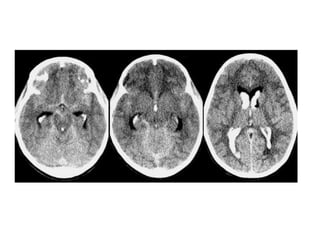

5. Diagnóstico:

RECONHECIMENTO DO RN DE RISCO ( PT <32 sem na UTI )

– USG;

• 3º dia de vida

• 7 º dia de vida

– GRADUAÇÃO DA SEVERIDADE

• Hemorragia na MG

• Hemorragia intra-ventricular sem DV

• Hemorragia intra-ventricular com DV

• Ecodensidade periventricular

Grading system Severity of GMH/1VH Description of findings

Papile I Isolated GMH (no IVH)

II IVH without ventricular dilatation

III IVH with ventricular dilatation

IV IVH with parenchymal hemorrhage